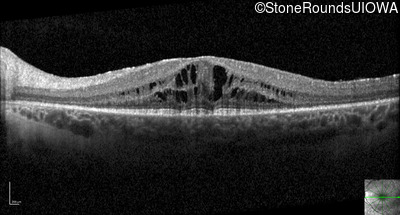

Optical Coherence Tomography - Left - 20/32

Exemplar / OCT Stack

OCT Stack